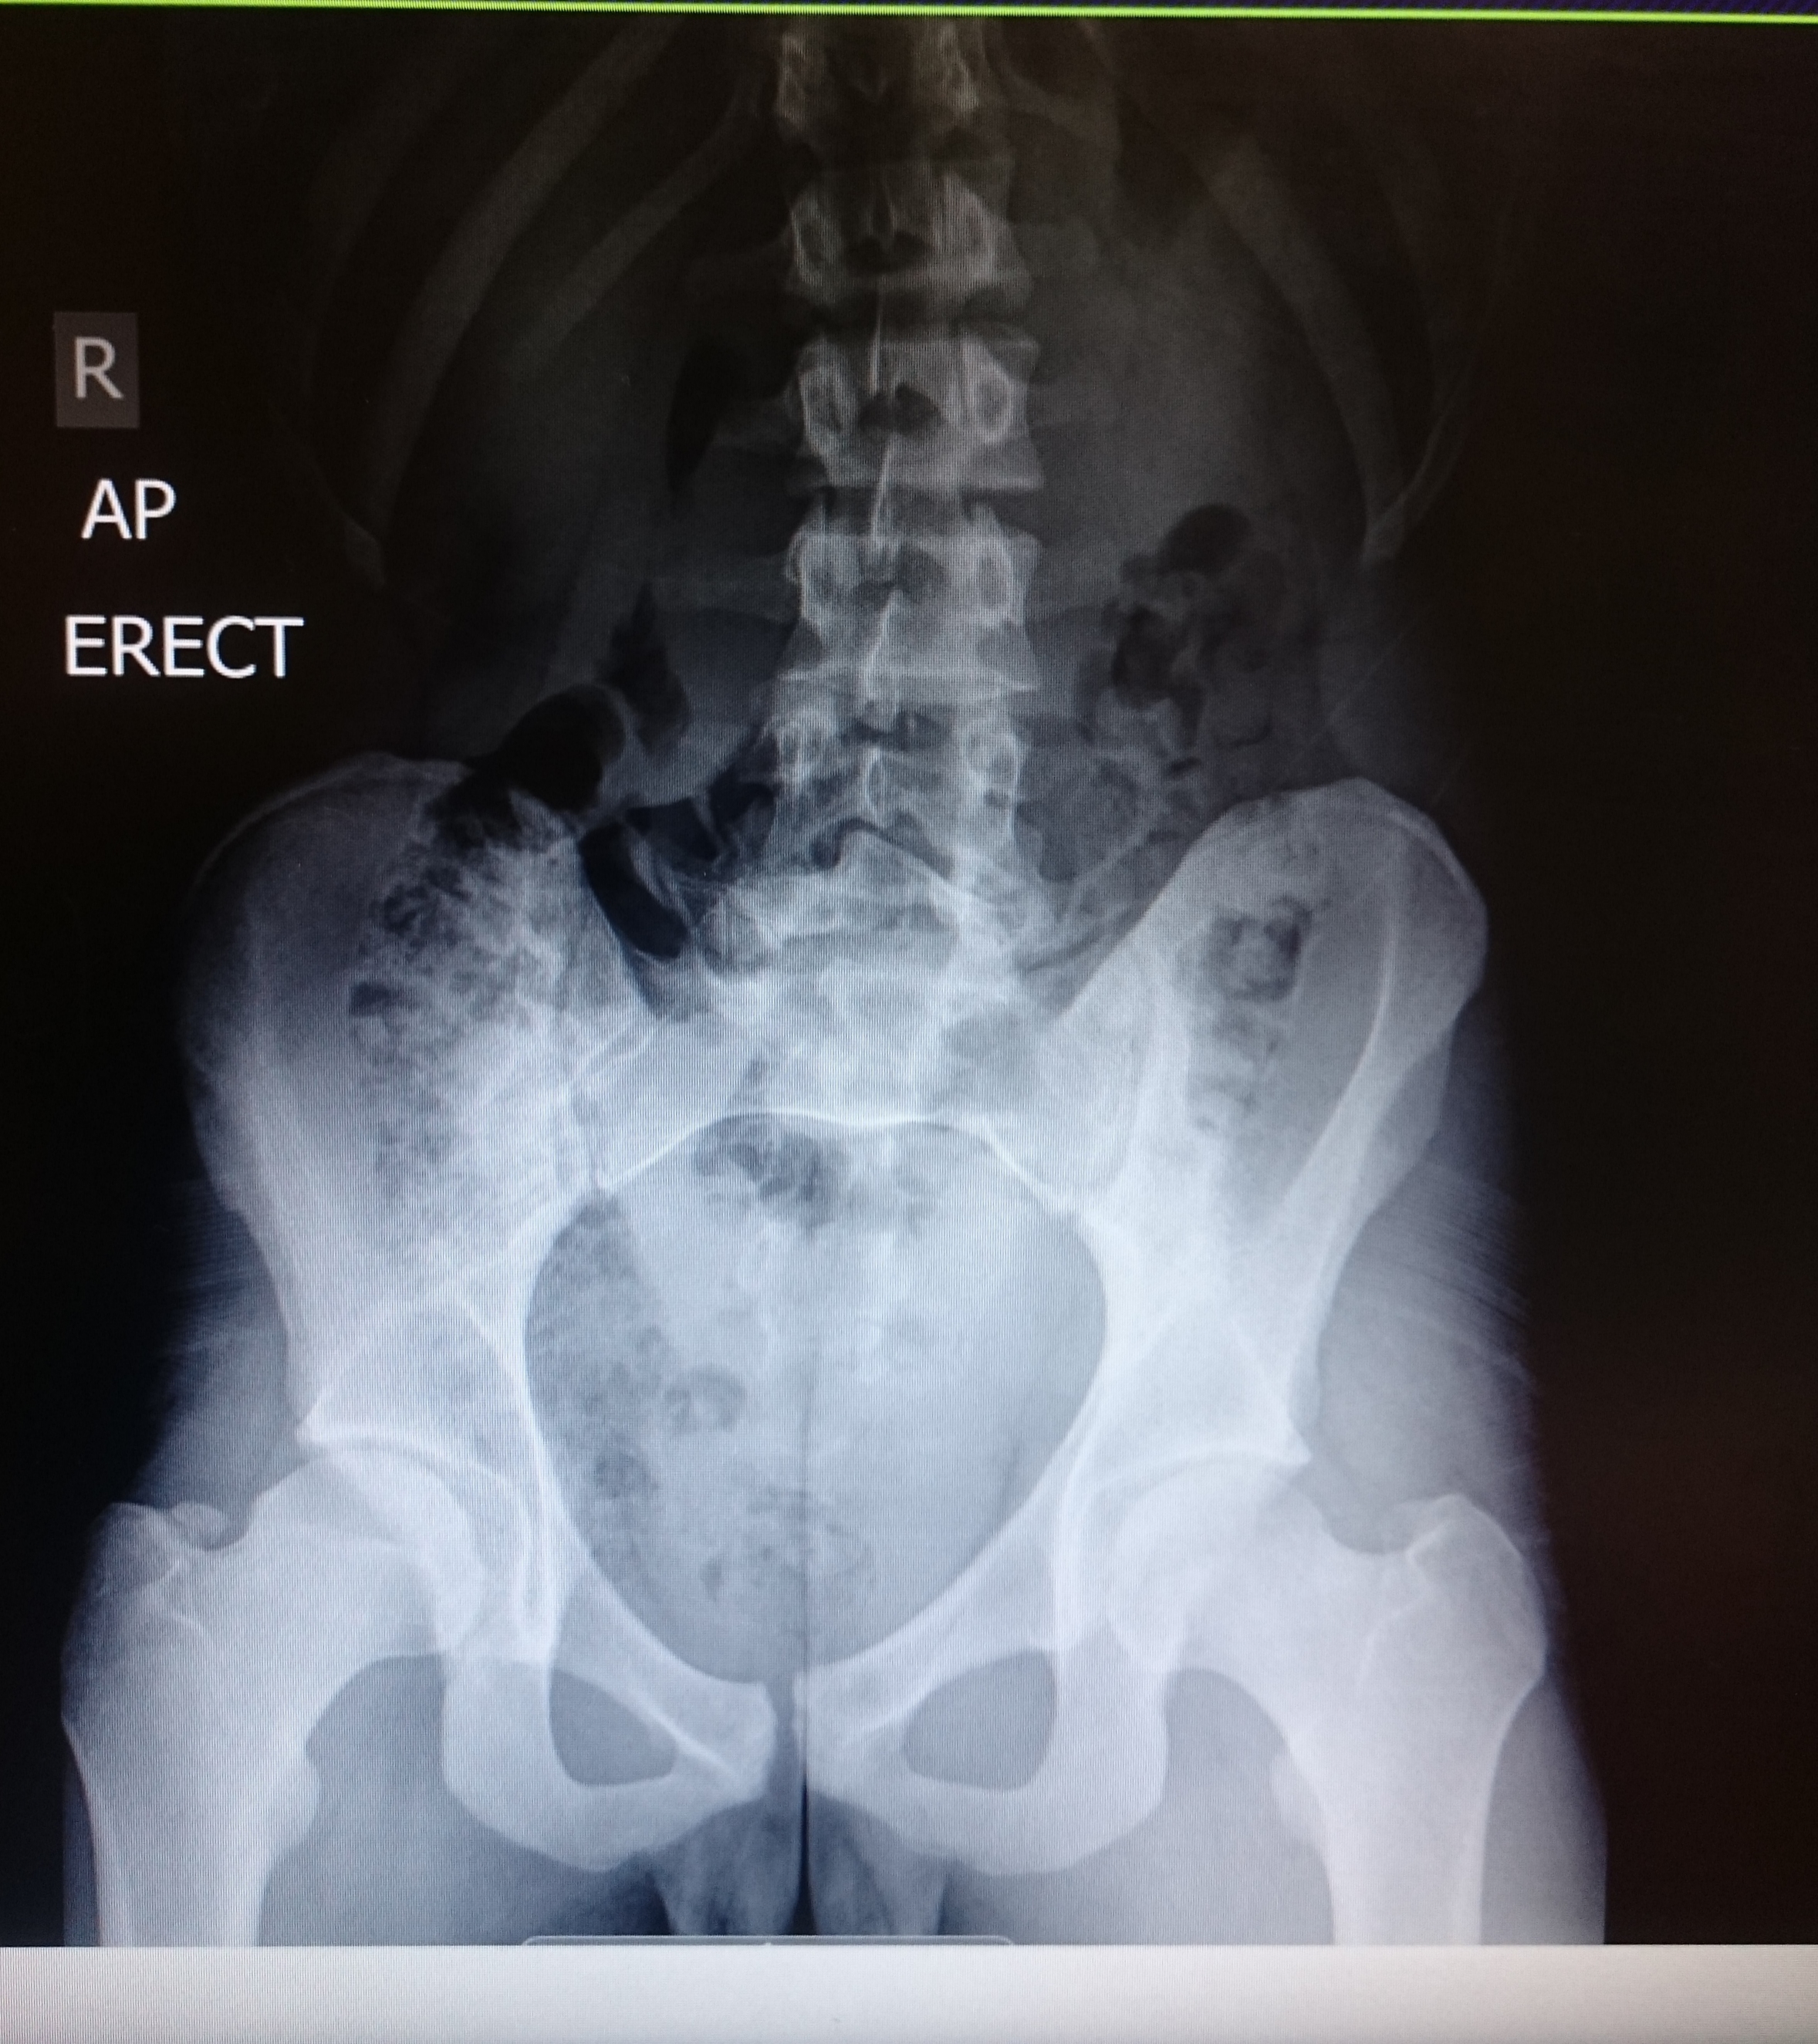

09/10/2015 - After finally seeing a consultant at the Nuffield, he says that my pain is a referred pain from a schmorl herniation in a vertebral disc. Schmorl herniation's (are protrusions of the cartilage of the intervertebral disc through the vertebral body endplate and into the adjacent vertebra) also for a number of years I have noticed that my hips are slanted but I have thought this was due to the way in which my growth spurt as a teenager had lead me, but this is actually down to a PARS fracture. http://www.pamf.org/sports/harriss/parsstressfractures.pdf

The Fracture is thought to be an old rugby injury or mountain biking injury whereas the Schmorl hernation is part of a growing process which also effects teenagers.

A CT scan is now booked to look into the fracture within further detail. As for the herniation, the pain should subside within another 6-12months by itself. I have now started light training to regain my physical appearance.

After waiting over a month to finally get my CT Scan results back, it has been confirmed that I have a PARS fracture. The scans confirmed that I was born with an abnormal vertebra which may have fractured a number of years ago. The left side has also started to fracture due to taking all of the stress from rugby, mountain bike falls, heavy deadlifts/squats etc. I have started training and decided to do a 12 week transformation.